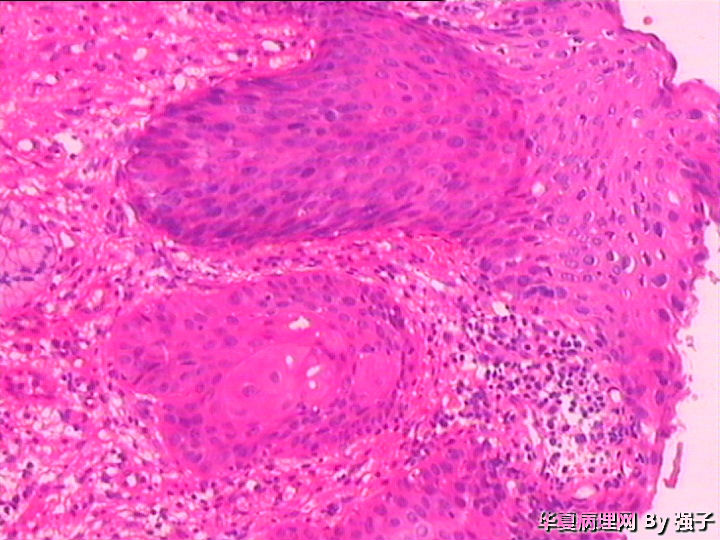

紧急求助,化生?还是累腺?

女,29岁

属于CIN病变吧,有累及腺体的地方,患者还满年轻!

高级别上皮内瘤变,累腺

高级别上皮内瘤变,累腺,第4图有核分裂

CINII-III累腺,学习中

CIN2级累腺